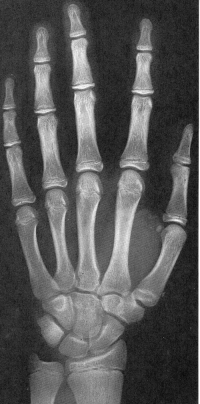

Sexo Masculino

Recém-Nascido

idade óssea - RN